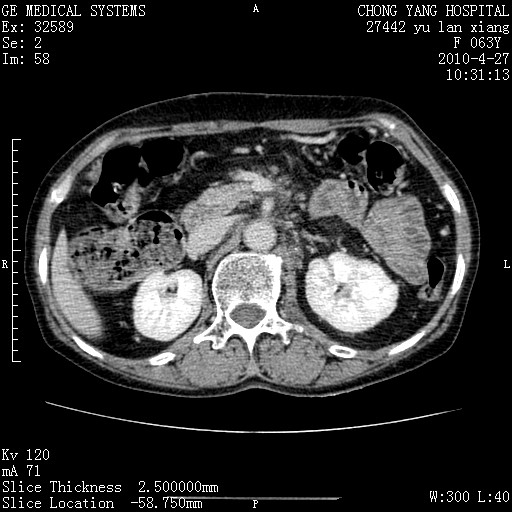

标题: CT26066:F63Y 上腹正中压痛半月,CA199:7400u/ml,MR示胰腺炎伴 [打印本页]

胰腺癌侵犯腹腔动脉干-分支、胃壁、左侧膈肌伴胰周及腹膜后淋巴结转移、胆囊切除术后。

胰腺癌侵犯腹腔动脉干-分支、胃壁、左侧膈肌伴胰周及腹膜后淋巴结转移、胆囊未显影。